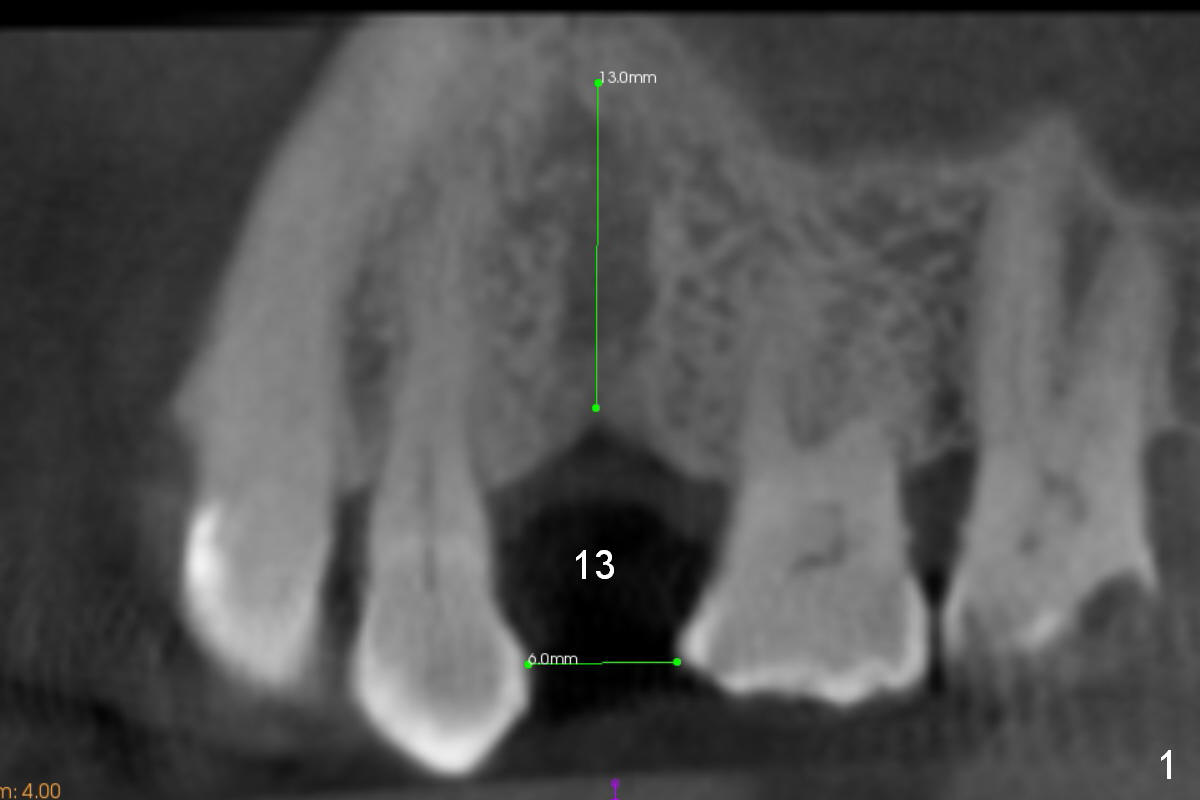

A 74-year-old man has diabetes. Implant osteointegration appears to be slow at #4, while the implant at #28 failed once. He requests implant at #13 (Fig.1). It seems that the bone is wide enough (8 mm, Fig.2 (CT coronal section) (P: palatal)) to hold a 4 mm implant (Fig.3 (axial section)). Since bone density is low at the coronal (100-200 units) and middle (50-100 units) segments (Fig.2), bone condensation will be beneficial. To facilitate wound healing, flapless approach is adopted using 1.6 mm pilot drill (Fig.4), followed by 1.4/2.6 mm bone expander. In fact there is resistance to expansion in the zone 1. Magic expander (3.0 mm) is also tried with difficulty. It appears that bone density is higher than expected. The second portion of Magic Surgical Kit is then used: 3.3 mm Magic Drill for 15 mm (gingival level, followed by Final Drill). A 4x13 mm IBS implant is seated incompletely. The osteotomy is further enlarged by 3.8 mm Magic Drill for 11 mm and deepened with 3 mm drill until 18 mm. Finally the implant is placed at a satisfactory level with insertion torque > 50 Ncm (Fig.5). A 4.5x4(3) mm abutment is placed and periodontal dressing is applied. The patient chooses to return for impression 6 months postop (Fig.6). The abutment changes to a 4x4(4) mm one. The crown is recemented nearly 2 years post cementation, which is related to distal and deep placement of the implant and bruxism (Fig.7).